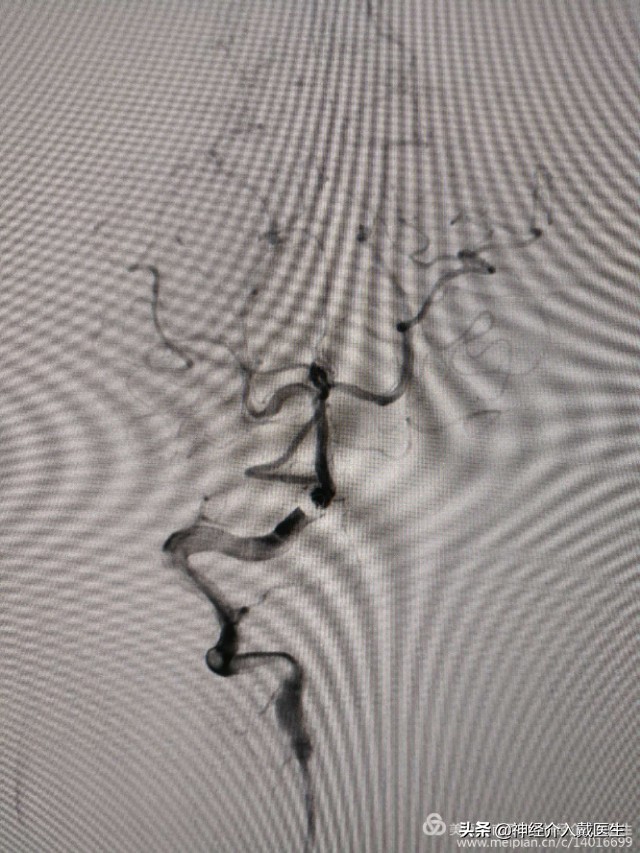

复查椎动脉正位,动脉瘤不显影,载瘤动脉及右侧小脑后下动脉通畅。

复查椎动脉侧位,动脉瘤不显影,载瘤动脉及右侧小脑后下动脉通畅。遂结束手术。